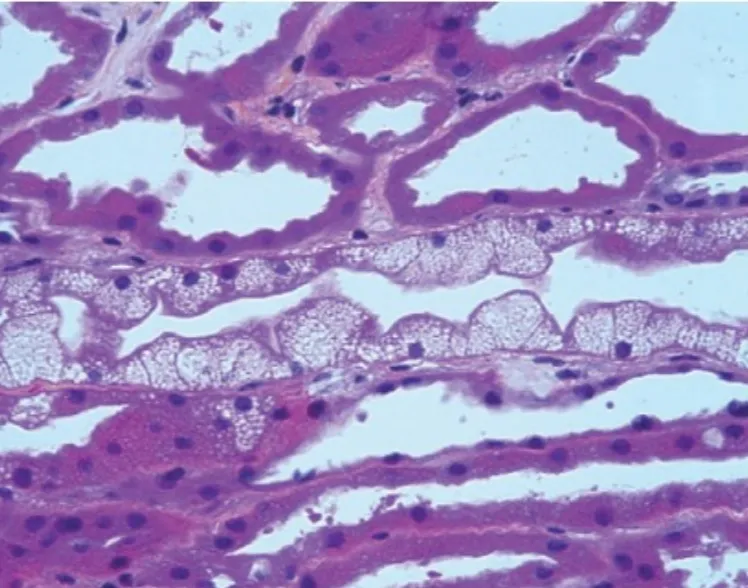

Desescalada de inmunosupresores en la Nefritis Lúpica

Desescalada de inmunosupresores en la Nefritis Lúpica